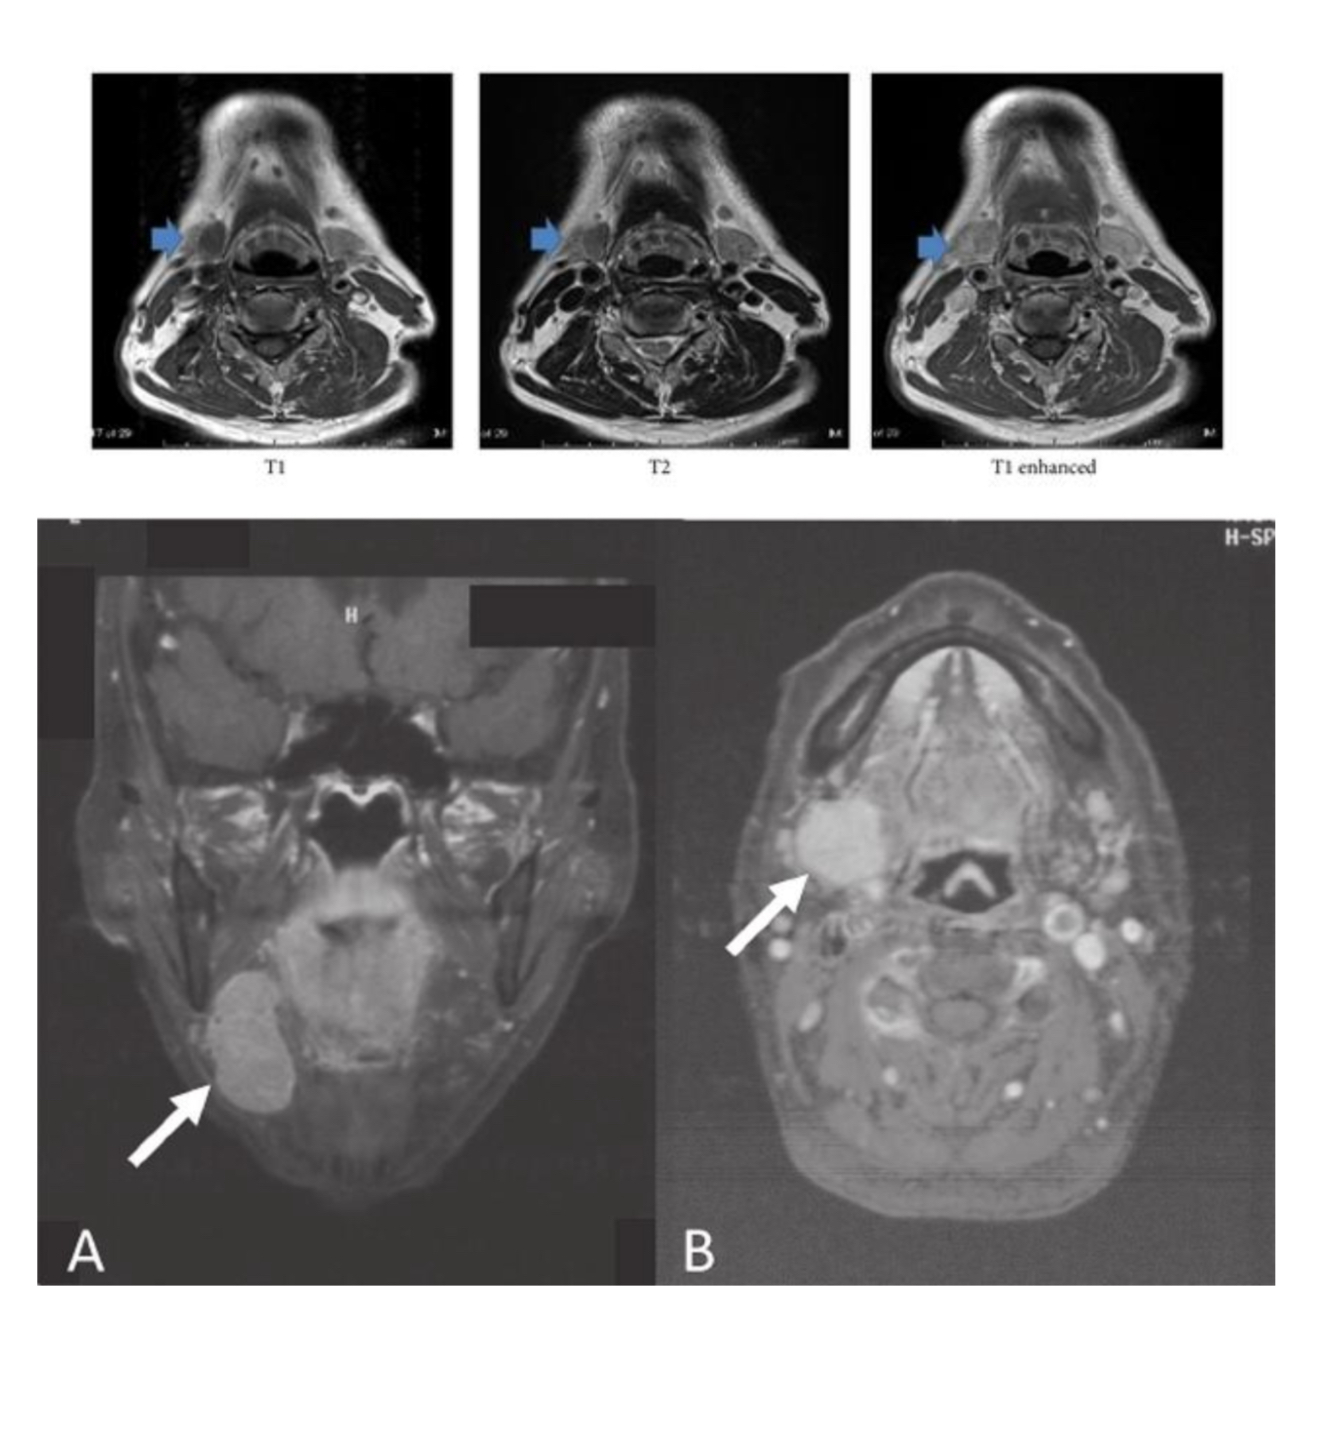

MATCH

Mandibular fossa

Condyloid process

Articular eminence

Articular disk

A

C - Mandibular fossa

D - Condyloid process

A - Articular eminence

B - Articular disk